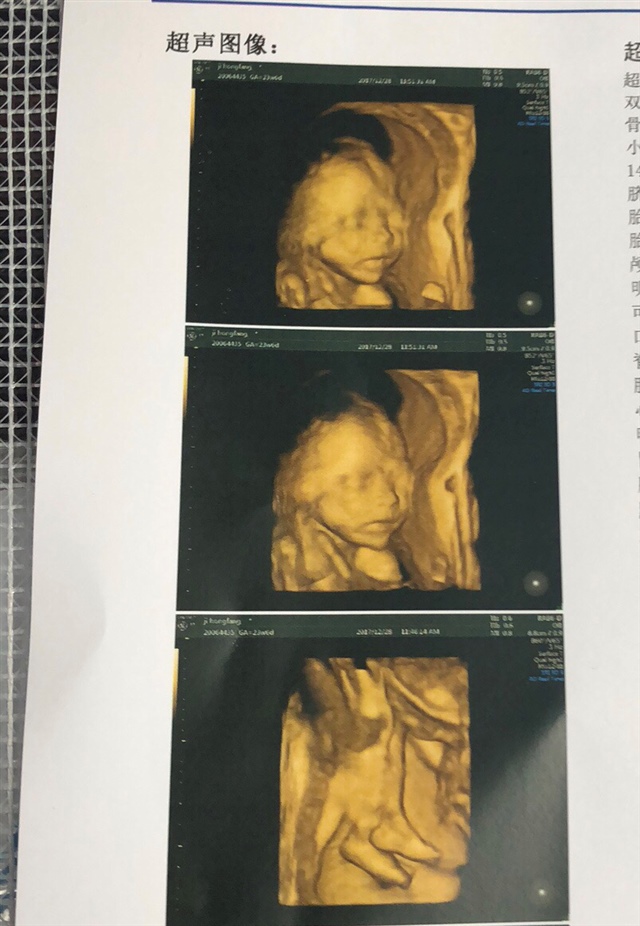

23周就做了4维了吗?